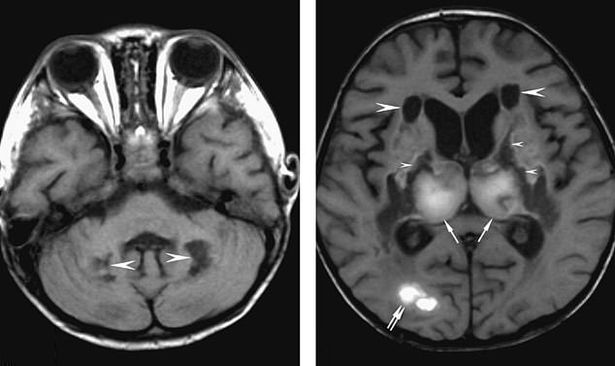

医生对她的大脑进行了CT扫描,显示出暗点,检查表明这名女子的大脑有液体堆积,并且脑细胞大量死亡。

患者的丘脑(最重要的感觉传导接替站)显示出严重的损伤,而其他扫描也显示该妇女大脑损伤或颞叶出血。